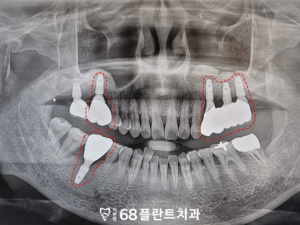

파노라마 사진을 촬영하여

확인해보니,

오른쪽 위 치아는

치아가 상실되었으며

왼쪽 위, 오른쪽 아래 어금니들이

잇몸병으로 인해

뼈가 많이 녹아있는 상황이었습니다.